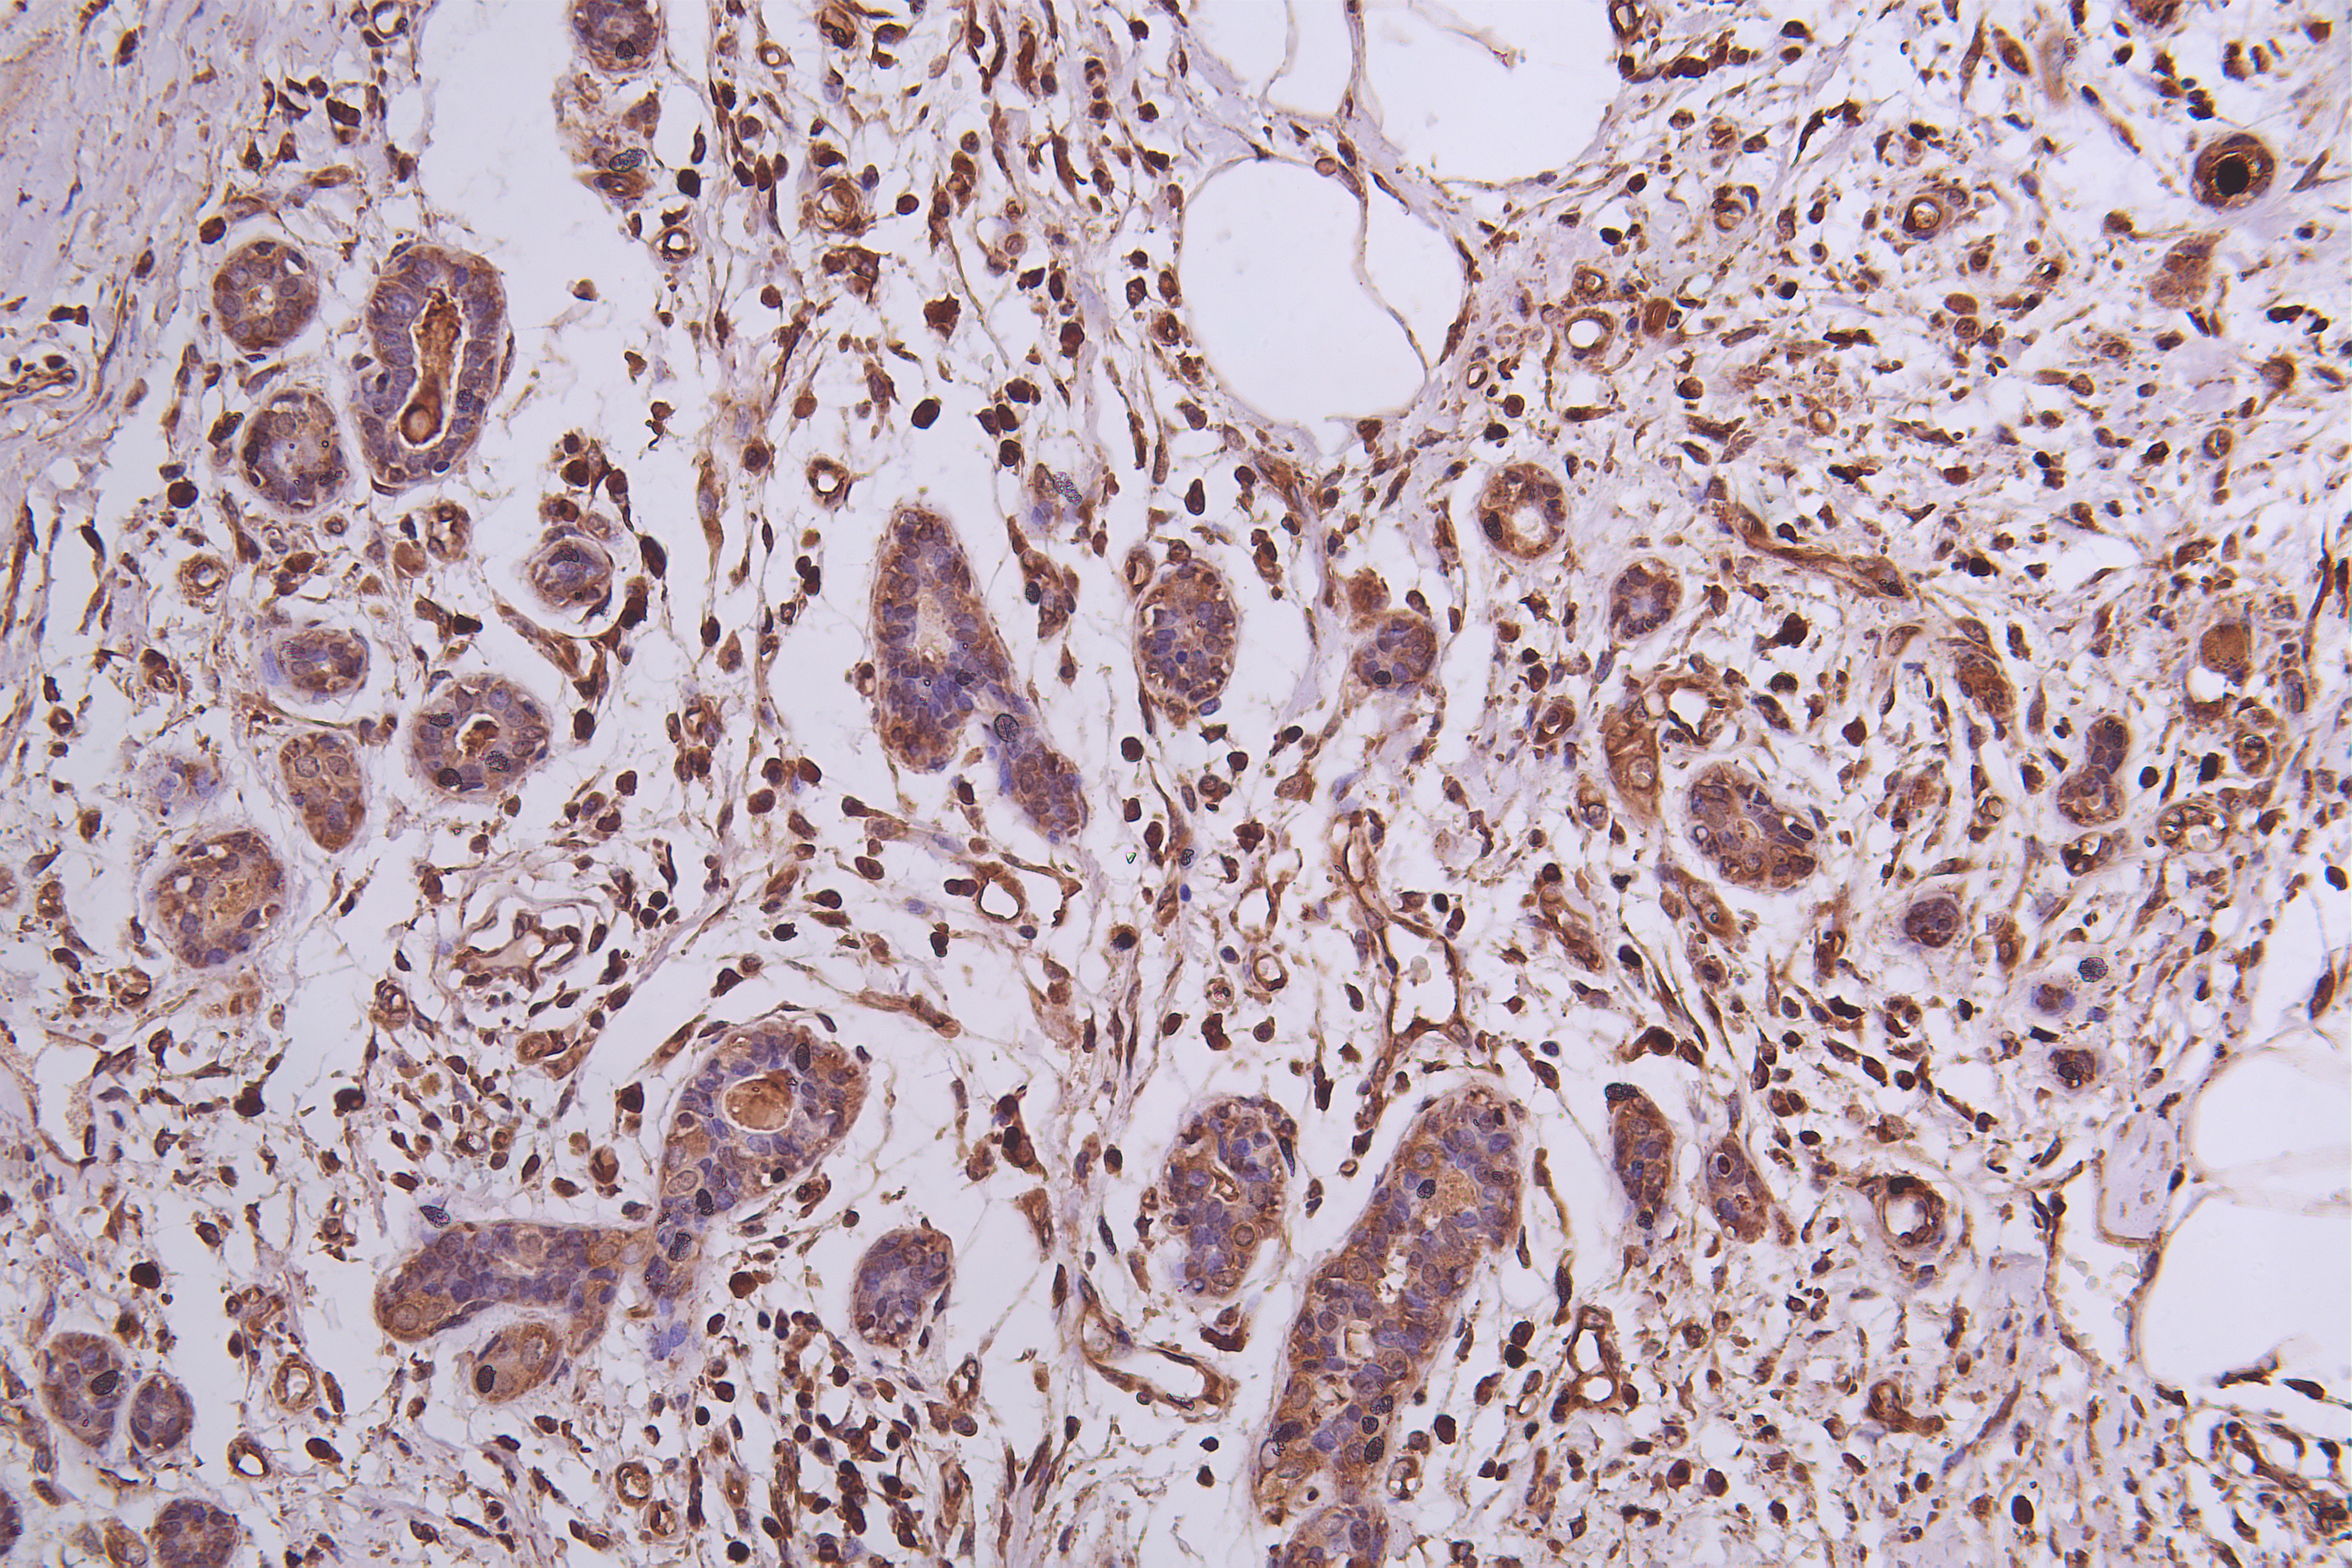

Immunohistochemistry of paraffin-embedded human Breast cancer using CSB-PA704858ESR1HU at dilution of 1:50